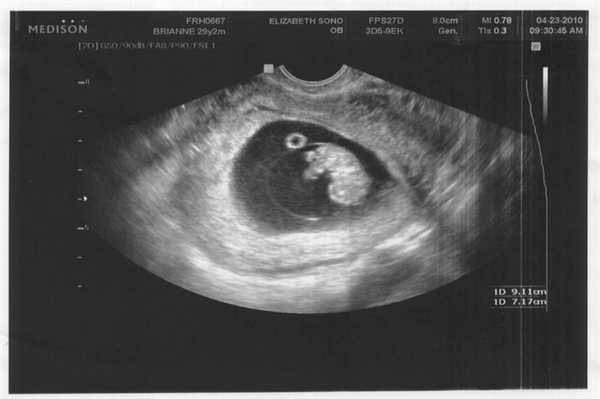

Фото УЗИ ребенка на 7 неделе беременности

Все части тела малыша растут, он распрямляется и вытягивается. Размер эмбриона достигает 10-13 мм. У него формируются очертания лица, появляются первые еле заметные движения конечностями. На снимке врач может отчетливо увидеть контуры малыша, несмотря на его маленькие размеры. Ультразвуковое исследование на таком маленьком сроке может определить замирание развития плода и угрозу выкидыша. Патологии не определяются.

Фото УЗИ ребенка на 8 неделе беременности

У плода формируются изгибы коленей, локтей, пальчики. Длина эмбриона достигает 20 мм, он распрямляется, у него образуется шея. У девочек в это время происходит закладка тканей яичников, а у мальчиков - яичек. Однако определить пол малыша на УЗИ невозможно, поскольку наружные половые органы еще не сформированы.

По снимку ультразвукового аппарата можно определить такие параметры:

- сердцебиение малыша (достигает 150 ударов в минуту);

- эмбрион имеет четкие очертания человека;

- видны пальчики рук, которые малыш может сжимать и распрямлять;

- увеличиваются размеры матки и плодного мешка;

- увеличивается объем околоплодных вод.

Фото УЗИ ребенка на 9 неделе беременности

В этот период происходит активное формирование структур мозга, в частности гипофиза и мозжечка. Нижние и верхние конечности удлиняются, у малыша появляются почки и печень. Также идет закладка черт лица. Пол ребенка еще не определяется, однако в организме плода начинают вырабатываться половые клетки - яйцеклетки у девочек и предшественники сперматозоидов у мальчиков. Размеры плода можно сравнить с размерами крупной вишни.

На УЗИ врач четко видит многоплодную беременность, а также определяет место прикрепления плодов. Сердцебиение хорошо прослушивается. На снимке не видны патологии и пол ребенка.